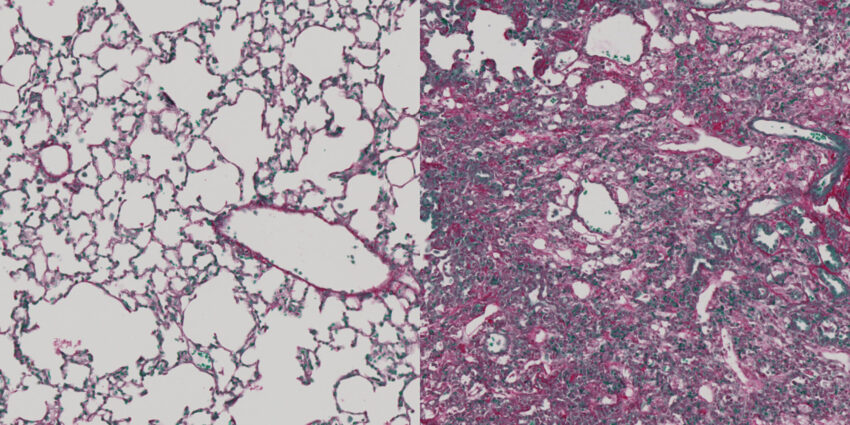

Scarring and fibrosis result from the secretion and accumulation of collagens between cells, typically as a response to injury or damage. Excessive collagen production can lead to fibrotic tissue, which can compromise the function of tissues and even entire organs. Approximately 45% of deaths in industrialized countries are linked to tissue fibrosis.

The team tested the peptides on normal human fibroblasts and observed a decrease in collagen export, with the effect being reversible within 48 hours. Similar results were obtained when testing fibroblasts from scleroderma patients and in zebrafish experiments.